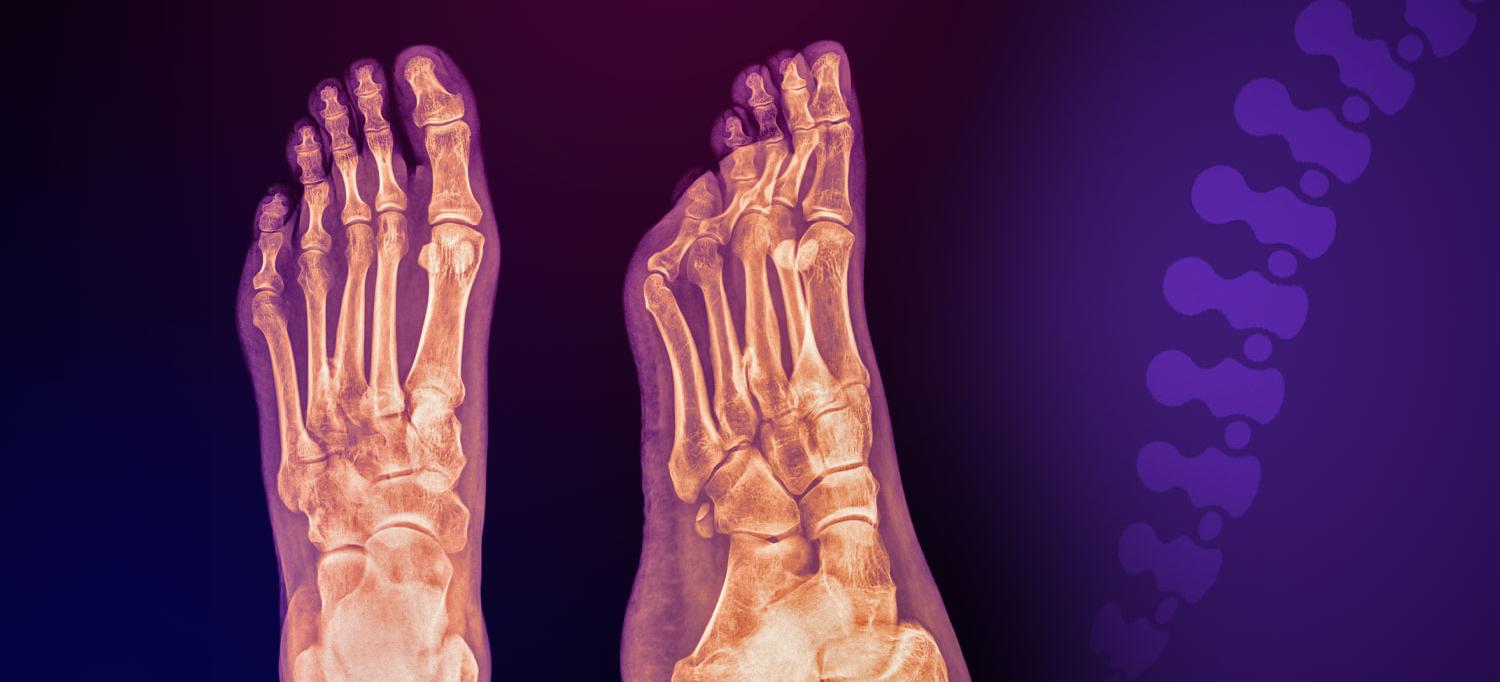

Plantar fasciitis, as shown in this X-ray, can be excruciating, but there are a variety of effective ways to treat it.

In this episode, Lauren E. Borowski, MD, and Rick Delmonte, DPM, discuss the anatomy of the plantar fascia and plantar fasciitis, including causes and treatment options ranging from physical therapy and orthotics to more advanced methods, like plasma-rich platelet injections, shockwave therapy, and surgery.